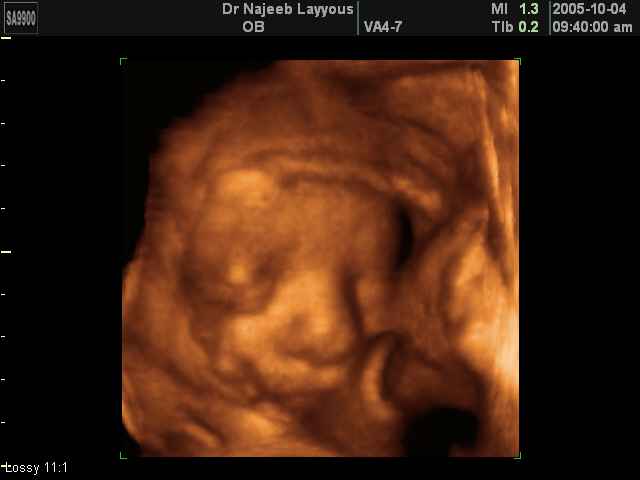

صور لتصرفات الجنين داخل الرحم بجهاز الالتراساوند ثلاثي الأبعاد | الدكتور نجيب ليوس

صور بجهاز الموجات فوق صوتية ثلاثي الأبعاد لتصرفات الجنين داخل الرحم